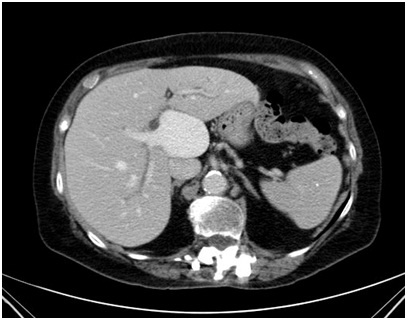

Giant Portal Vein Extra Hepatic Aneurysm: An Uncommon Finding

MartÃn MS et al.

Journal of Digestive Diseases and Hepatology